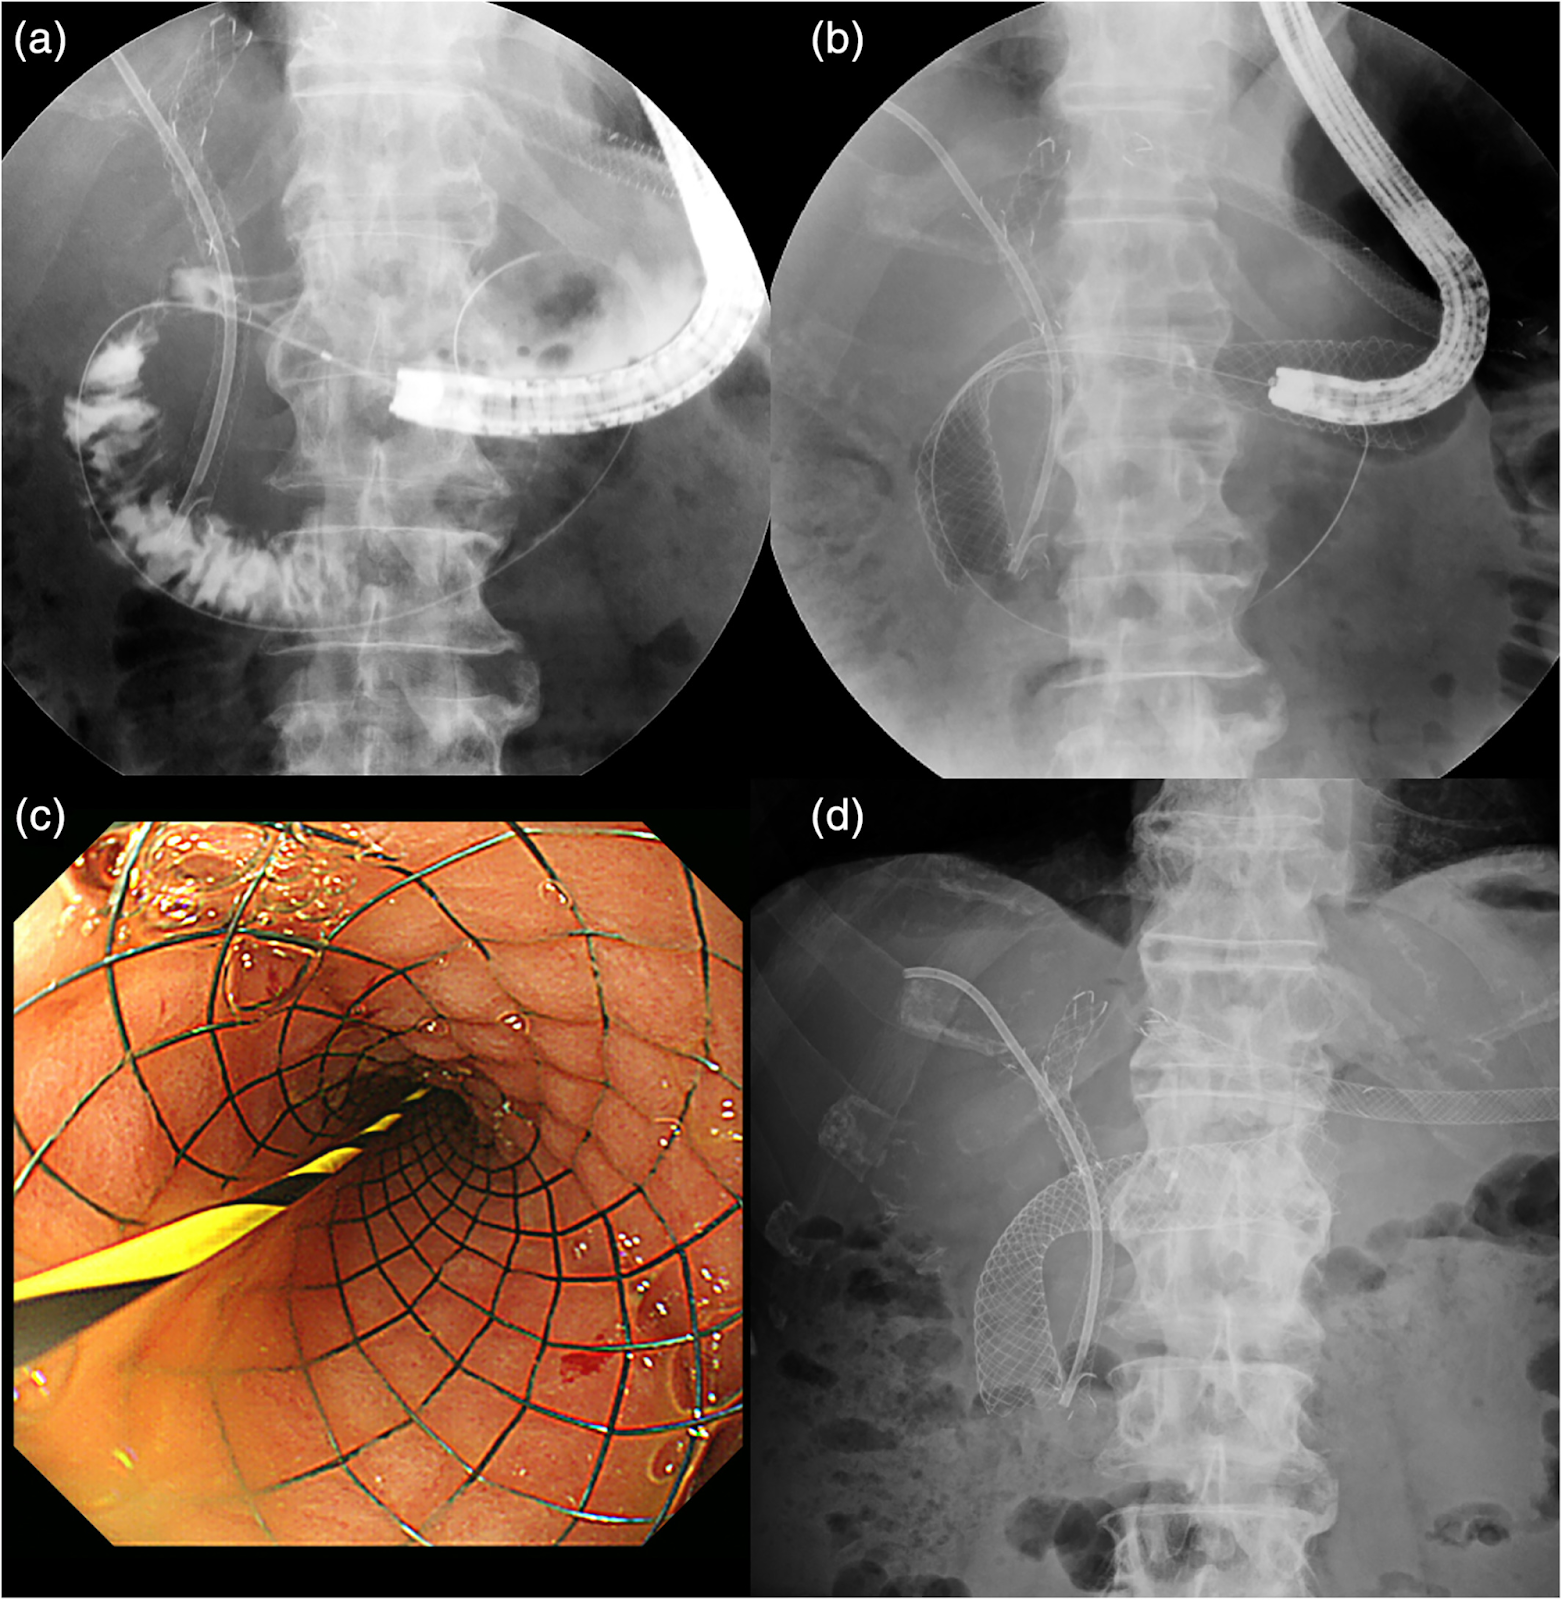

Стентирование двенадцатиперстной кишки выполняется путем гастродуоденоскопии (ФГДС) с помощью специального эндоскопа и струны-проводника, по которой стент заводится в область сдавленной двенадцатиперстной кишки. Процедура и положение стента контролируются с помощью рентгена.

Стентирование холедоха выполняется посредством эндоскопической ретроградной холангиопанкреатографии (ЭРХПГ) с помощью специального эндоскопа, струны-проводника и в сопровождении рентген-контроля.